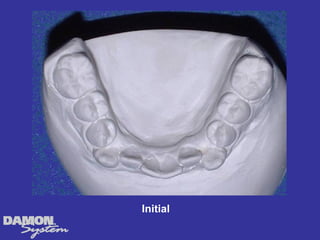

Width Initial Final Change Cuspid 32 mm 34.5 mm 2.5 mm 1st bicuspid 35 mm 43.5 mm 8.5 mm 2nd bicuspid 41 mm 48 mm 7 mm 1st Molar 48 mm 52 mm 4 mm

Initial Final Note change in shape of the palate โ€“ tongue can now move into balance